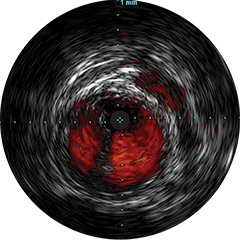

Digitale IVUS- Bildverarbeitung

Abbildung 1

Abbildung 2